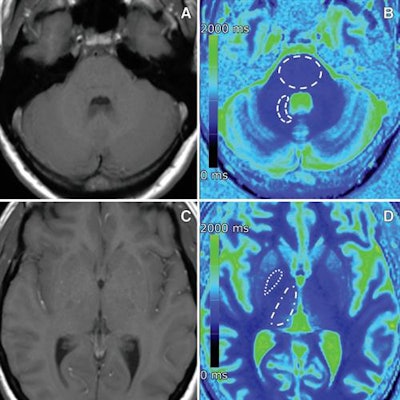

All 220 subjects underwent unenhanced MRI brain scans on a 1.5-tesla MRI scanner (Magnetom Aera, Siemens Healthineers). The protocol included T1-weighted spin-echo and T1 and T2 mapping to determine visual signal-intensity changes; signal-intensity ratios of the globus pallidus to the thalamus and the dentate nucleus to the pons; and T1 and T2 relaxation times. In MRI terms, relaxation refers to how signals can weaken or broaden over time. T1 mapping helps calculate the loss of signal, while T2 mapping conveys broadening of the signal.

The results showed no visual changes or differences in signal-intensity ratios or in T1 and T2 mapping between the patient groups.

However, there were significantly shorter T1 relaxation times in the globus pallidus among patients with normal renal function and multiple administrations of gadobutrol, compared with control subjects with normal renal function. The difference between the two groups was 226.2 msec (p = 0.002).